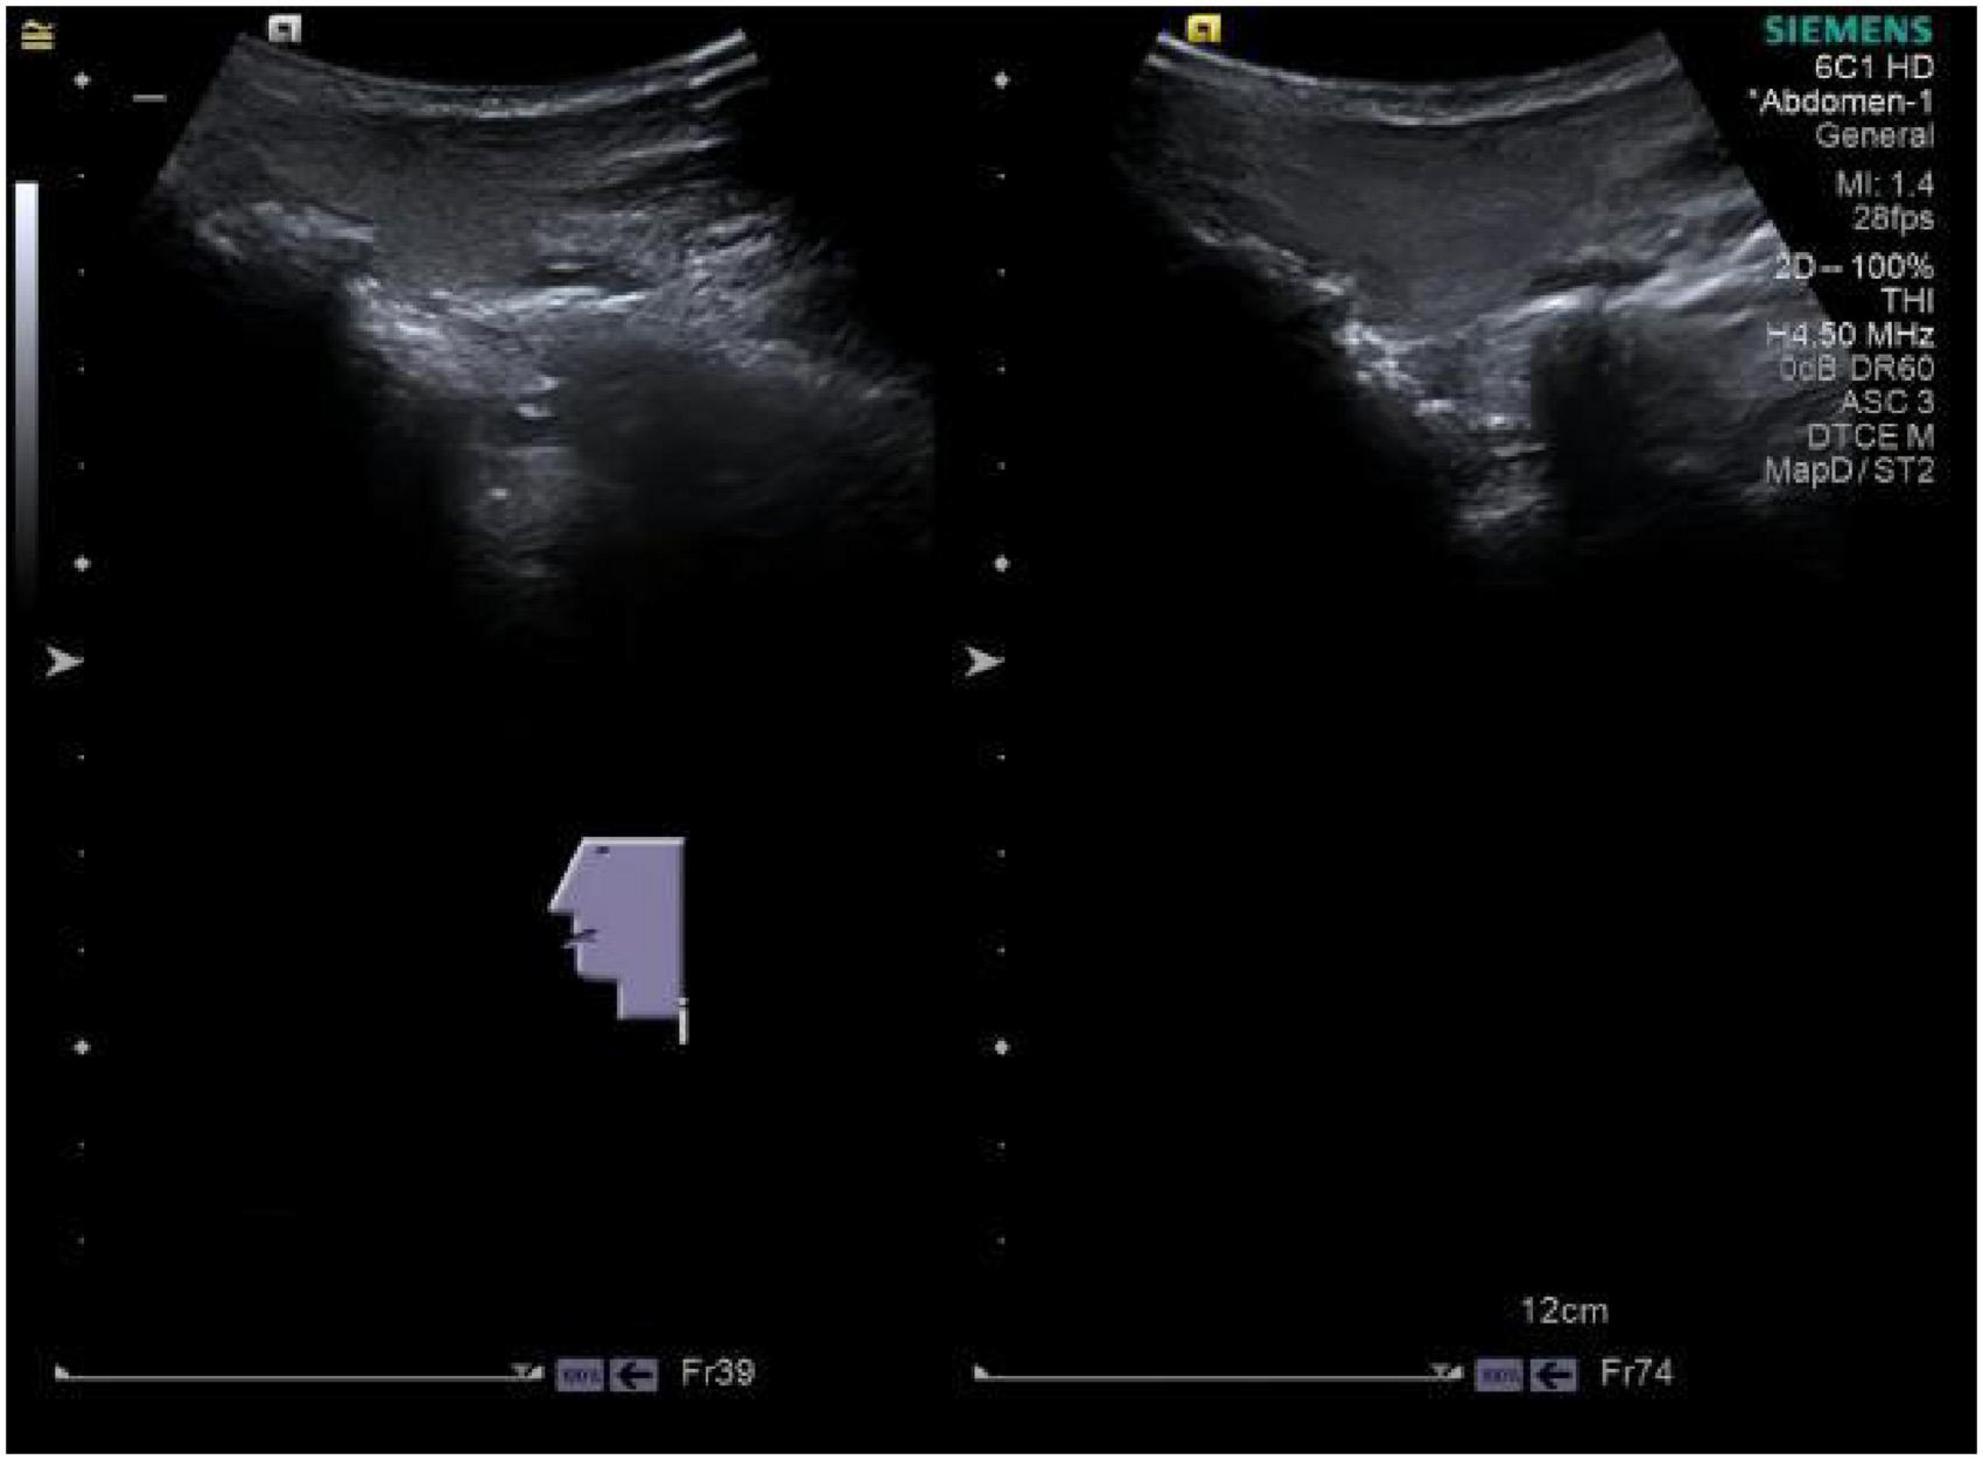

Background Madelung's disease (MD) is a rare disorder of fat metabolism, with symptoms often characterized by the appearance of chronic accumulations of abnormal adipose tissue in areas such as the neck and neckline, upper back and chest. Nowadays, its pathogenesis is still unknown, and some scholars have suggested that its etiology is closely related to alcohol consumption, and that it is associated with a variety of metabolic diseases such as liver disease, hypertension, diabetes mellitus, dyslipidemia, and peripheral neurological damage. Currently, there are very few reported cases of Madelung's disease complicated by alcoholic liver disease and liver cirrhosis (LC), making this case worthy of reporting. Case summaries This article reports on a 60-year-old man, the main point of view"The patient has experienced edema in both lower limbs for two weeks , accompanied by a long history of alcohol consumption".Clinical examination showed subcutaneous swelling of the neck, which has been clearly present for three years. The diagnosis of Madelung's disease combined with alcoholic liver disease and liver cirrhosis was made based on laboratory tests of liver function, ultrasound of the neck vessels, ultrasound of the superficial tissues of the neck, and CT of the abdomen. The patient has not exhibited restricted neck mobility or symptoms of tracheoesophageal fat syndrome, which affects swallowing and breathing, and refused neck surgery treatment and received hepatoprotective therapy and traditional agents. After 14 days and two cycles of Chinese medicine,edema subsided, and the size of the subcutaneous mass remained stable. Result Madelung's disease is often underdiagnosed and misdiagnosed because of its low prevalence. The purpose of this article is to illustrate the need to be vigilant in clinical encounters with patients with Madelung's disease combined with alcoholic liver disease and liver cirrhosis, to achieve early intervention and treatment, and to prevent complications. The etiology of this disease remains unclear. Further research into its pathophysiological mechanisms should be pursued, opening new avenues for therapeutic investigations.